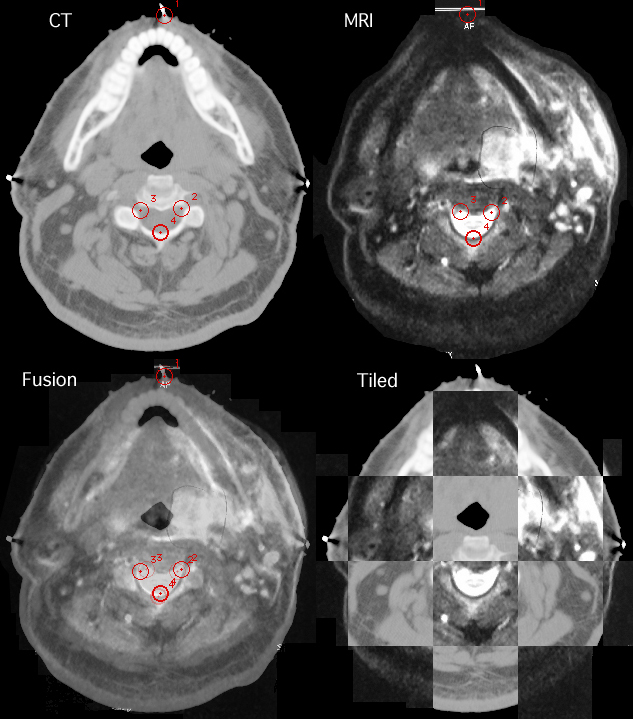

This is an example of CT and MRI fusion. An axial CT image from a DICOM file was opened and selected as image "A". An approximately equivalent axial MRI slice was obtained by photographing a film on a viewbox (using a Nikon megapixel digital camera) and saving the image as a JPEG (.jpg) file. The MR file was opened and selected as image "B". Equivalent points-of-interest (POI) were created on the two images and then the images fit by scaling and rotating and then fused. Also illustrated is the use of the tiling tile slider slider as an alternative method of merging images.